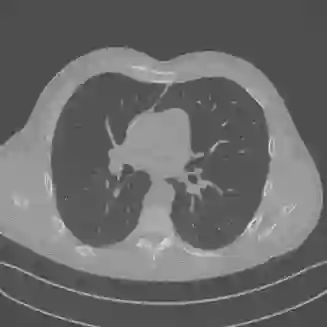

Low-Dose Computed Tomography (LDCT) technique, which reduces the radiation harm to human bodies, is now attracting increasing interest in the medical imaging field. As the image quality is degraded by low dose radiation, LDCT exams require specialized reconstruction methods or denoising algorithms. However, most of the recent effective methods overlook the inner-structure of the original projection data (sinogram) which limits their denoising ability. The inner-structure of the sinogram represents special characteristics of the data in the sinogram domain. By maintaining this structure while denoising, the noise can be obviously restrained. Therefore, we propose an LDCT denoising network namely Sinogram Inner-Structure Transformer (SIST) to reduce the noise by utilizing the inner-structure in the sinogram domain. Specifically, we study the CT imaging mechanism and statistical characteristics of sinogram to design the sinogram inner-structure loss including the global and local inner-structure for restoring high-quality CT images. Besides, we propose a sinogram transformer module to better extract sinogram features. The transformer architecture using a self-attention mechanism can exploit interrelations between projections of different view angles, which achieves an outstanding performance in sinogram denoising. Furthermore, in order to improve the performance in the image domain, we propose the image reconstruction module to complementarily denoise both in the sinogram and image domain.